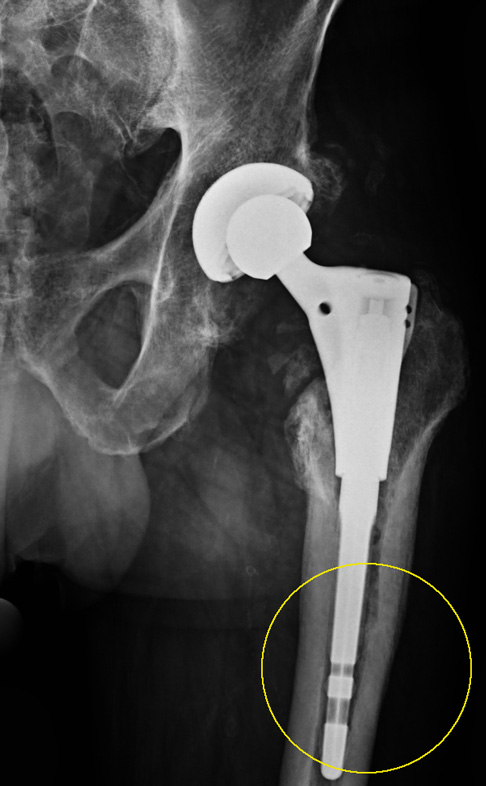

Bei der Prothesenplanung ist es für ein dauerhaft gutes Ergebnis entscheidend, die Pfannengröße und Schaftlänge optimal auf die anatomischen Gegebenheiten des Patienten anzupassen. Das Röntgenbild der Hüftprothese zeigt ein mechanisches Problem, das zu einer frühen Lockerung geführt hat: Die Schaftlänge wurde hier nicht optimal gewählt und der Zementmantel um die Prothese ist nicht ganz gleichmäßig. Der Oberschenkelknochen zeigt in der Höhe des Trochanters, einem seitlichen Knochenvorsprung des Oberschenkelknochens (Markierung 1), eine deutlich verminderte Knochendichte. Die Tragfähigkeit des Femurs (Oberschenkelknochen) ist also bereits vermindert. Der zementierte Prothesenschaft hat sich aufgrund der ungünstigen Geometrie gelockert und ist im Markraum des Oberschenkels verkippt. Eine schmerzhafte Sinterung (Einsinken der Prothese in den Oberschenkel) mit Beinlängenverkürzung ist die Folge. Der Patient konnte ohne Gehhilfe nicht mehr gehen. Seine maximale Gehstrecke war infolge der gelockerten Hüftprothese stark eingeschränkt.

Für die Wechseloperation wurde eine Prothese mit einem einwachsendem Langschaft, der tief im Oberschenkelknochen verankert ist, gewählt. Dies entlastet den geschwächten Trochanter (seitlicher Knochenvorsprung des Oberschenkelknochens). Tiefere Anteile des Oberschenkels beteiligen sich an der Last. Keramischer Ersatzknochen verstärkt die Knochenbildung am Trochanter, damit sich die Knochensubstanz in diesem Bereich wieder regeneriert. Der Patient war nach der Wechseloperation wieder beschwerdefrei.